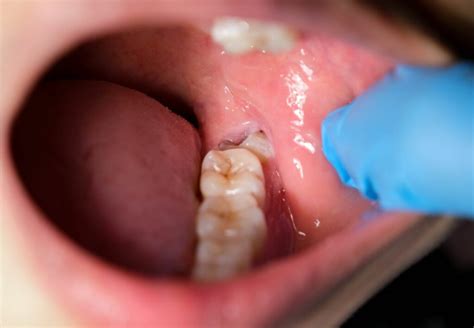

Pericoronaritis: Inflamación de la Encía por la Salida de la Muela del Juicio

Es decir, se produce cuando una muela del juicio ha comenzado a erupcionar y le falta espacio para salir, quedando una parte de esta cubierta por encía. La pericoronaritis es la inflamación de la encía por encima de la muela que no ha erupcionado totalmente. Inclusive causando dolor intenso al hablar y muchas veces limitación de la apertura bucal, dificultad al tragar, halitosis o mal olor de boca. Presencia de pus al tocar la encía alrededor de la muela del juicio.

La pericoronitis es debido a la escasez de espacio en el momento en que erupcionan las muelas del juicio. Estos restos de comida que quedan por debajo de la encía que cubre la muela parcialmente son los que causan la infección. Las encía que cubre la muela parcialmente erupcionada termina por convertirse en un hábitat idóneo para que las bacterias orales proliferen. Además del dolor intenso y permanente, deberemos hablar de otro tipo de síntomas que se presentan, como la fiebre.

Esto supone un dolor intenso que puede incluso dificultar la masticación o el hecho de abrir la boca. El surgimiento de esta infección está favorecido por la existencia de una higiene bucodental deficiente. Para reducir su infección recomendamos cepillar bien la zona y hacer enjuagues con Clorhexidina.

Inclusive causando dolor intenso al hablar y muchas veces limitación de la apertura bucal, dificultad al tragar, halitosis o mal olor de boca. Presencia de pus al tocar la encía alrededor de la muela del juicio. En casos graves, la pericoronaritis crónica puede causar dolor al masticar, al tragar o al abrir la boca completamente. Afectar al segundo molar. Otras zonas del cuerpo también se verán afectadas por esta infección, que tiene la particularidad de extenderse rápidamente.